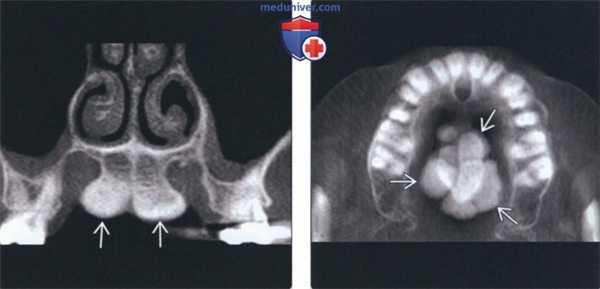

(Слева) На корональной КЛКТ визуализируется большой небный валик, разделенный посередине. Такие крупные валики могут приводить к нарушению функции и часто приводят к хронической травматизации, требуя удаления хирургическим путем. Покрывающая слизистая оболочка обычно истончена.

(Справа) На аксиальной КЛКТ у этого же пациента визуализируется мультицентрический небный валик. Обратите внимание на признаки доброкачественного роста: симметричное увеличение и ровные края.